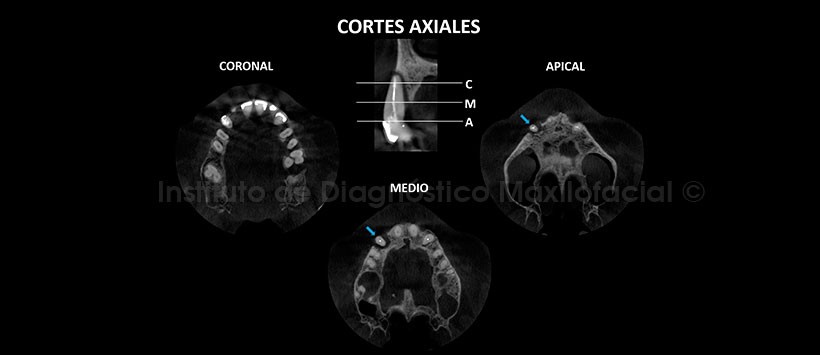

A la evaluación de la tomografía volumétrica (CBCT) en cortes axiales (Figura 2), transaxiales (Figura 3) y tangenciales (Figura 4), se evidencia reabsorción moderada del reborde dento-alveolar de la pieza 13 con presencia de defecto óseo peri-radicular de pieza dentaria 13 que ocasiona la pérdida de la tabla ósea vestibular.